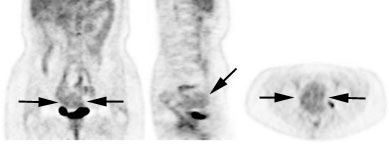

|

Genitourinary activity: The image below demonstrates activity within the collecting system of a transplanted kidney (black arrows). This should not be mistaken for an abnormality. |

|

|

|